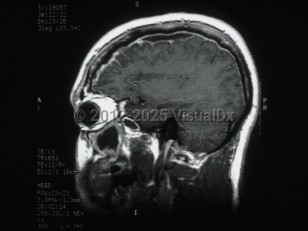

Subdural empyema is a collection of pus in the space between the dura and the arachnoid. Infection of the paranasal sinuses is a risk factor for cranial subdural empyema, as the infection can spread to the space by way of emissary veins. Contiguous spread of infection from osteomyelitis of the skull, meningitis, mastoiditis, or otitis media are also possible. Other etiologies include trauma, seeding of an existing subdural hematoma, or postoperative infection. These infections are typically polymicrobial.

Hematogenous seeding of the space is more likely to result in spinal subdural empyema. This location is less common, accounting for less than 5% of subdural empyema. Staphylococcus aureus is often implicated in infections in this location. Patients may present with fever, headache, and altered mental status (or some combination of these symptoms). Focal neurological signs and seizures may also be present. Magnetic resonance imaging (MRI) with contrast is the diagnostic test of choice.

Treatment is with a combination of surgical decompression and antibiotic therapy. Complications include cerebritis, cerebral abscess formation, and venous sinus thrombosis. Morbidity and mortality in subdural empyema is directly related to delay in therapy.